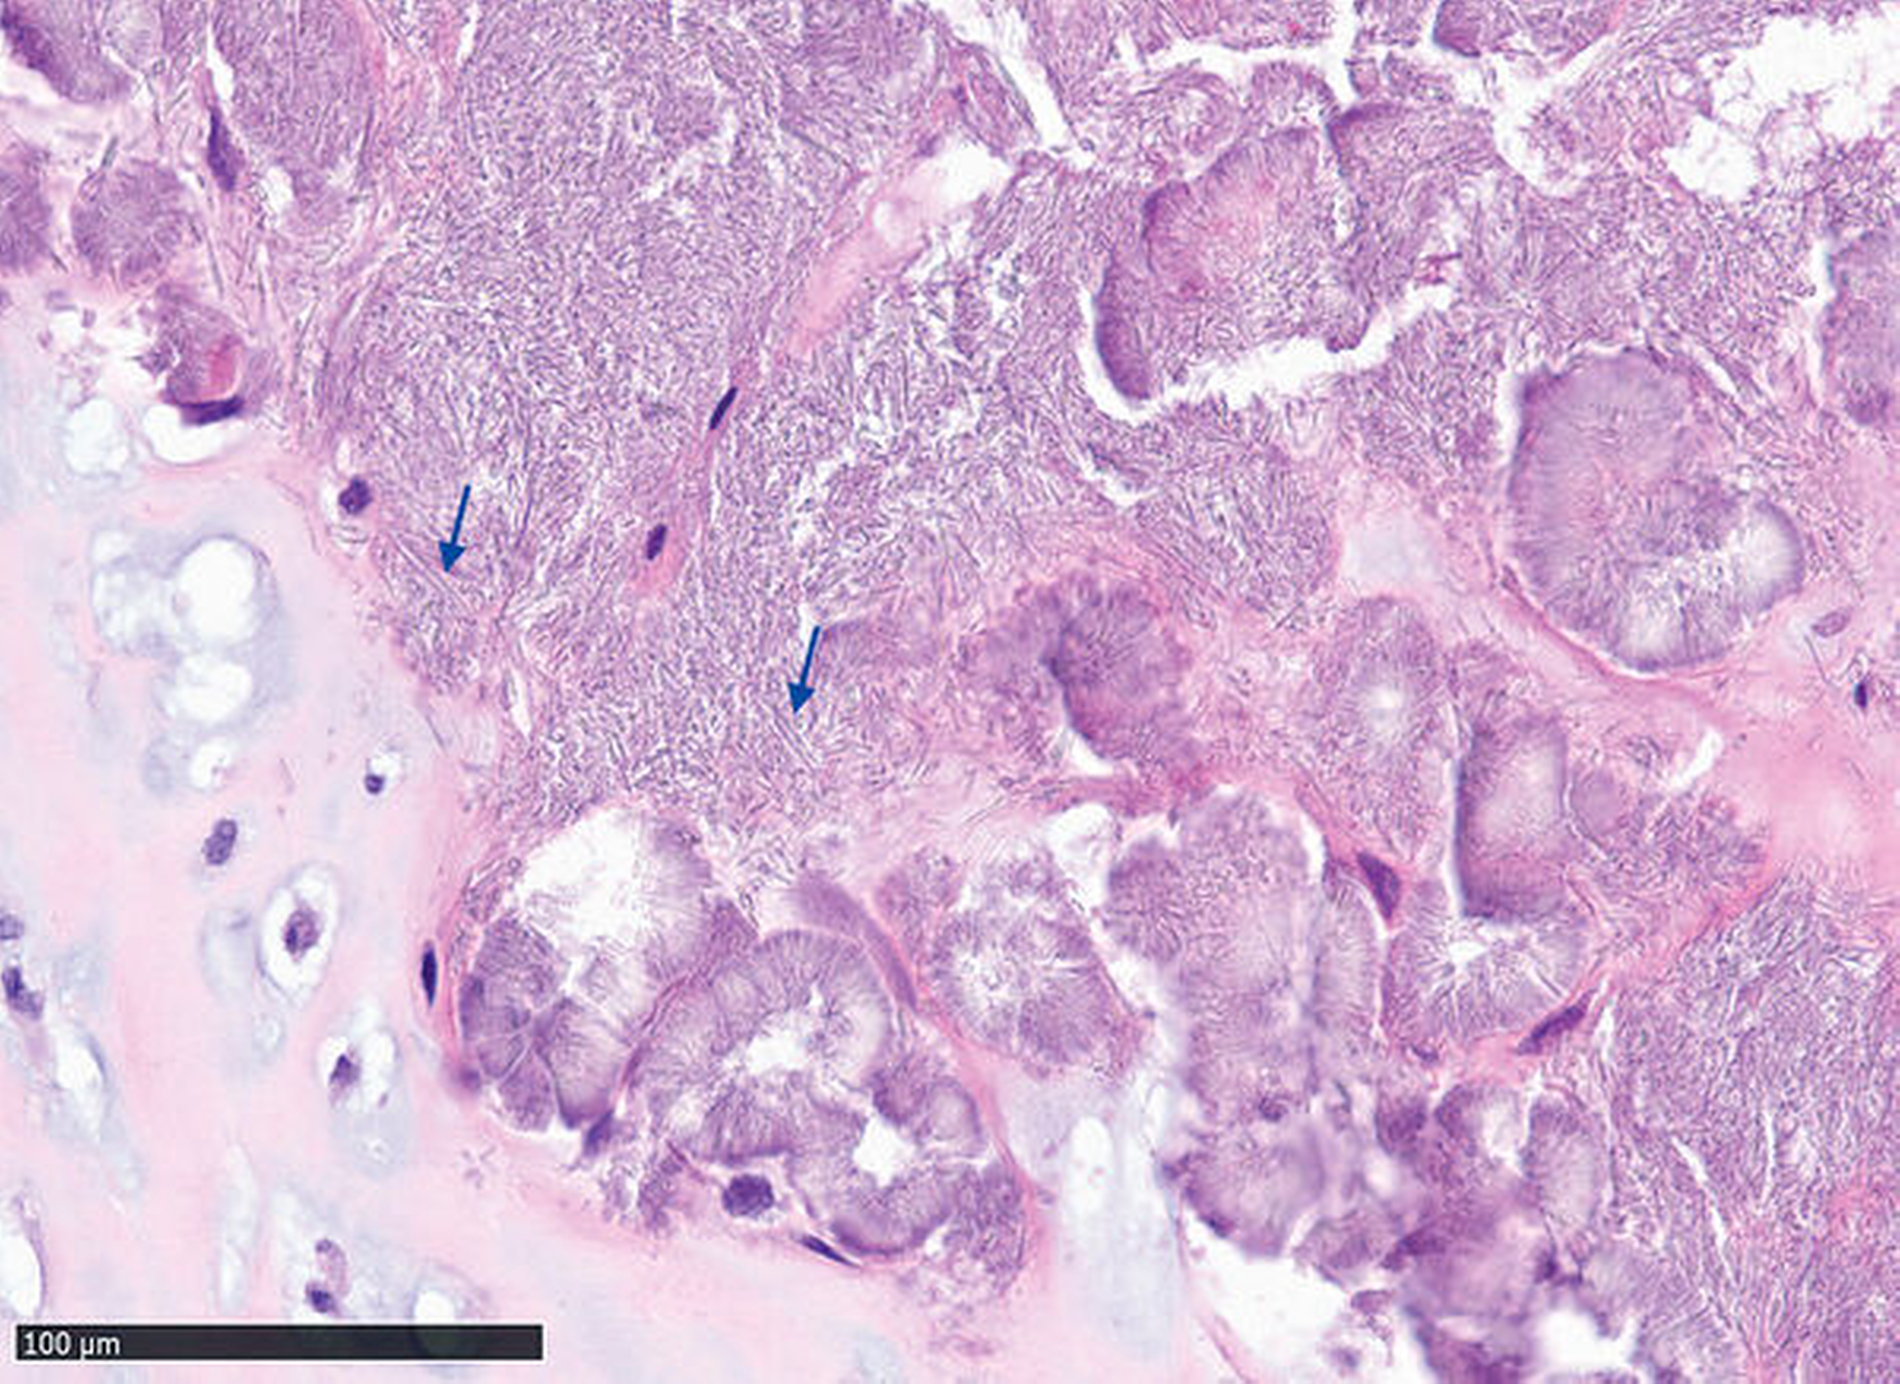

In der navigationsgestützten Probenentnahme in der darauffolgenden Woche präsentierten sich der perikapituläre Kapselapparat als solide kalzifiziert und verdickt sowie der Inhalt des Zystenkavums und die das Kiefergelenk umgebende Raumforderung – die soweit möglich entfernt wurde – als gallertartige Masse mit kleinen, kristallartigen Kalzifikationen (Abbildung 3). Die histopathologische Befundung zeigte die Charakteristika einer Kristallarthropathie mit assoziierter Fremdkörper- und Entzündungsreaktion, passend zu einer Kalziumpyrophosphat- Arthropathie (Abbildung 4). Nach unauffälligem postoperativem Verlauf konnte die Patientin entlassen werden. Im Rahmen der klinischen Untersuchung nach zwei Wochen unter Therapie mit einem nichtsteroidalen Antirheumatikum (NSAR) war sie bei vollständig regredienter Schwellung beschwerdefrei.

Während sich intra- und periartikuläre Verkalkungen gut mittels CT darstellen lassen, erfordert die Beurteilung der angrenzenden, oft neoplastisch anmutenden, aufgetriebenen, weichgewebigen und knorpeligen Strukturen eine ergänzende MRT-Untersuchung [Aoyama et al., 2000; Koitschev et al., 2003]. Mögliche, nur schwer abzugrenzende neoplastische Differenzialdiagnosen sind dabei das Osteochondrom, das Chondrosarkom oder das Chondroblastom [Loro und Bjørnland, 2020]. Wie im Fallbeispiel ist das – wenn auch seltene – Vorkommen kapitulär lokalisierter synovialer Zysten beschrieben [Maribo et al., 2019]. Synovialzysten sind echte synovial-ausgekleidete Zysten, die aus einer verlagerten oder exponierten Synovialschleimhaut entstehen und mit dem Gelenkkavum kommunizieren. Als Ursache vermutet man dabei eine primär traumatische oder postentzündliche Genese mit der Entstehung eines erhöhten intraartikulären Drucks [Vera-Sirera et al., 2013].

Da eine abschließende Bewertung der CPDD auf Basis radiologischer Daten nicht möglich ist, sollte die Diagnosestellung mittels histopathologischer Befundsicherung erfolgen. Wegweisend für die CPDD ist dabei der histologische Nachweis von Kalziumpyrophosphat-Kristallen. Aufgrund der unterschiedlich progredienten Verlaufsformen bedarf es verschiedener therapeutischer Ansätze. Zur Symptomkontrolle wird daher bei moderater Ausprägung die Gabe nichtsteroidaler Antirheumatika (NSAR), Colchicin sowie die intraartikuläre oder systemische Glukokortikoidgabe empfohlen [Koitschev et al., 2003; Announ und Guerne, 2007; Andrés et al., 2018]. Hingegen sollte bei fortgeschrittener Knochen- und Weichteilbeteiligung die chirurgische Entfernung der kalzifiziert-kristallinen Masse sowie des destruierten Knochen- und Weichgewebes zur Linderung der Beschwerden und Wiederherstellung der Funktion erfolgen [Meng et al., 2011; Kwon et al., 2018].